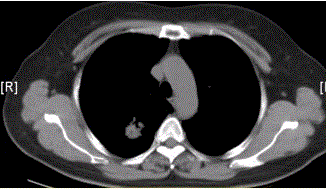

问题 患者女,54岁,无症状,常规体检透视时发现右上肺阴影。既往无结核病史。体格检查阴性。CT结果如下图。 本病例可见的征象包括

选项 A.分叶征 B.毛刺征 C.胸膜凹陷征 D.空泡征 E.含气支气管征 F.钙化

答案 ABCE